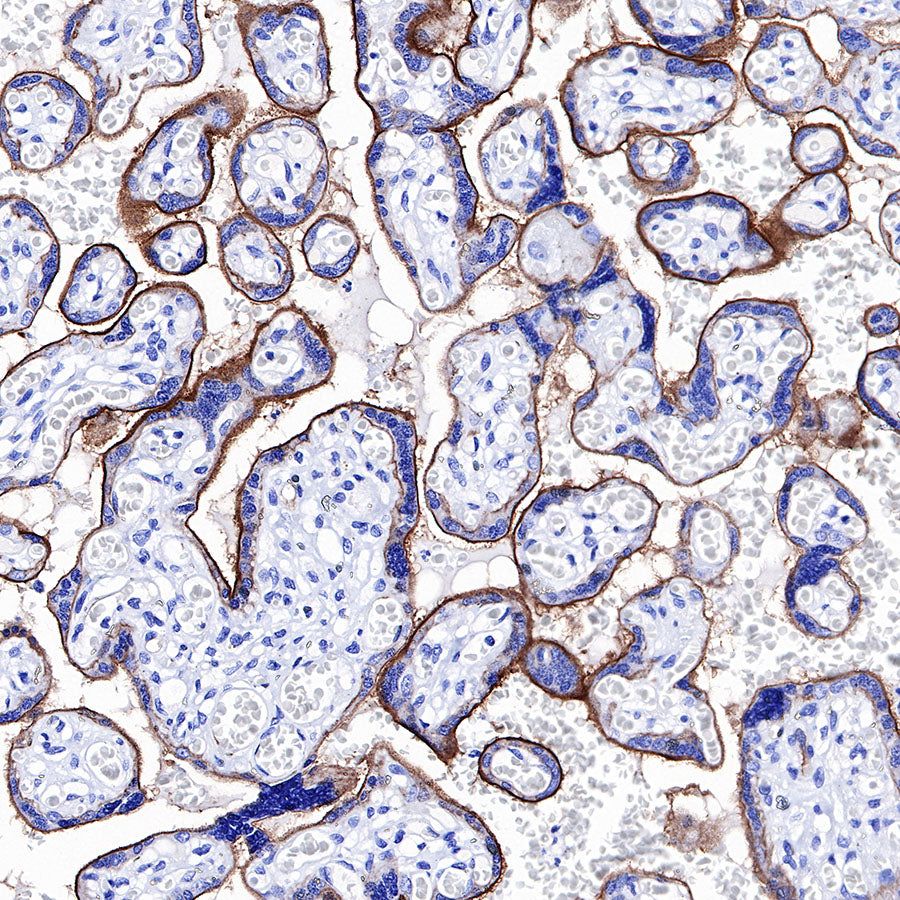

IHC shows positive staining in paraffin-embedded human placenta. Anti-CD39 antibody was used at 1/500 dilution, followed by a HRP Polymer for Mouse & Rabbit IgG (ready to use). Counterstained with hematoxylin. Heat mediated antigen retrieval with Tris/EDTA buffer pH9.0 was performed before commencing with IHC staining protocol.